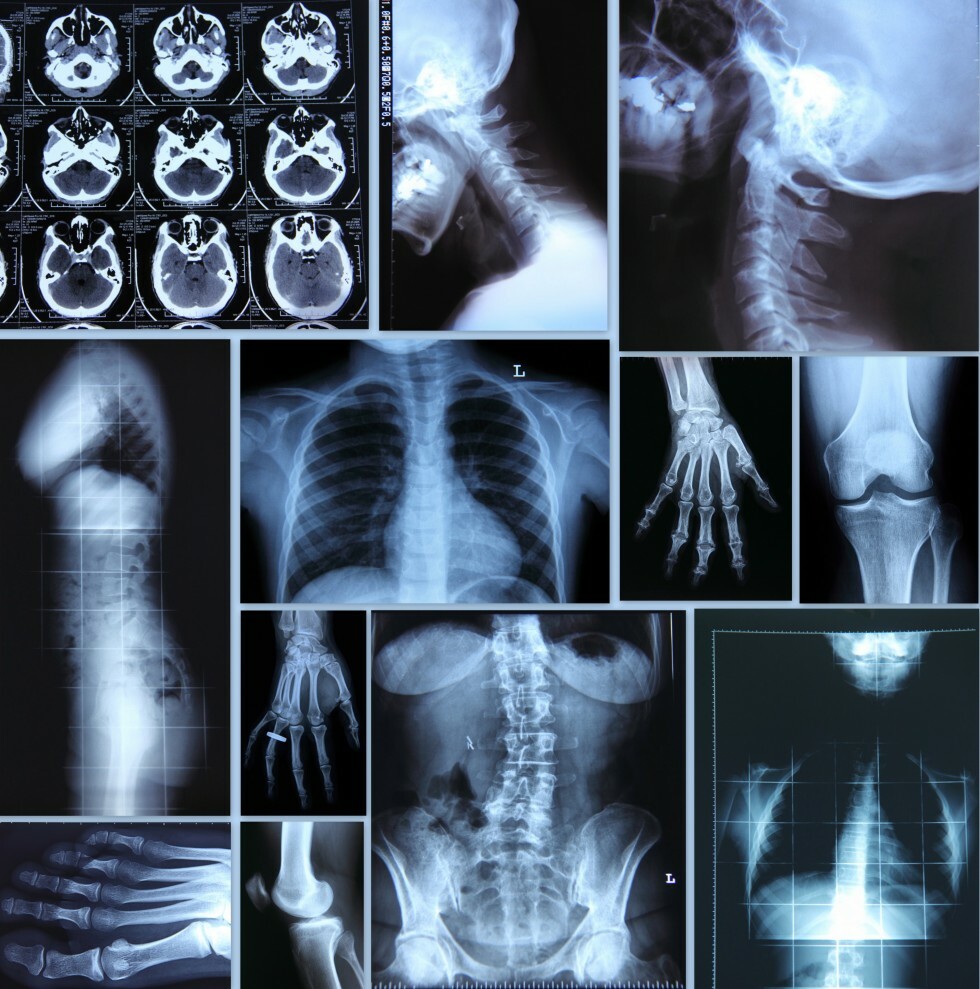

collage of xrays

The physicians of Professional Radiology, in conjunction with our partner hospitals, provide a full range of diagnostic radiology services.  We continuously investigate new procedures and techniques to better serve our patients.  We offer the latest technology and service in a variety of diagnostic areas including: